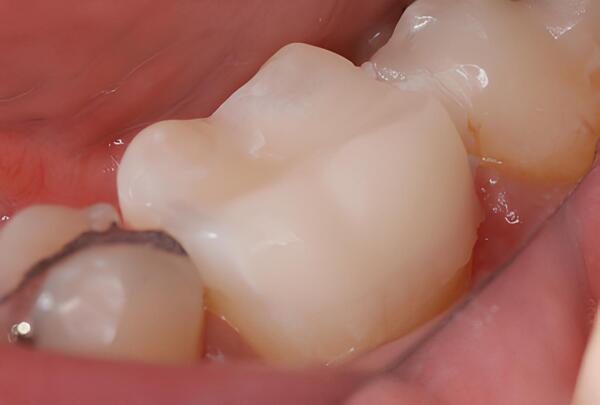

DENTISTERIE ESTHÉTIQUE : LES INLAYS ET LES INCRUSTATIONS

DENTISTERIE ESTHÉTIQUE : LES ONLAYS